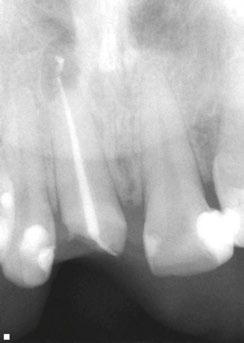

Figures 1A-1B: Two periapical radiographs of tooth No. 24 taken at different angles. Resorptive defect changes position relative to root canal, which according to buccal object rule, means defect is separate from canal and, hence, external to canal

While external root resorption comes in many forms, such as transient surface resorption, pressure resorption, external inflammatory root resorption, invasive cervical root resorption, and replacement resorption (ankylosis), internal root resorption is uniquely different. The differential diagnosis is made by taking multiple radiographs at different angles.9,10 Utilizing the buccal object rule, a lesion of internal origin will remain close to the canal regardless of the angle, while a lesion of external origin will move away from the canal depending on the angle of the radiograph (Figures 1A and 1B).

Additionally, with IRR, the outline of the root canal is usually distorted and appears contiguous with the resorptive defect, while with external resorption, the root canal outline appears normal and can usually be seen running through the radiolucent resorptive defect, as there remains a thin layer of dentin separating the canal from the resorptive area9-10 (Figures 2A-2D).

Figures 2A-2D: 2A: Periapical radiograph of tooth No. 21. Large resorptive defect is noted in external cervical region. Blue arrows point to a thin layer of predentin that appears to be running through defect. Outline is what remains of root canal wall. Tooth tested vital, and diagnosis of invasive cervical root resorption was made. Due to minimal remaining tooth structure, extraction was advised. 2B-2D: Sagittal, coronal, axial slices show resorptive defect external to root canal